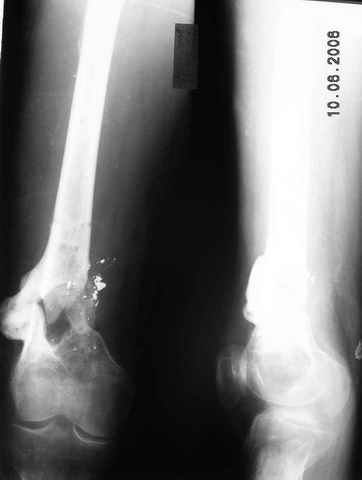

Возможно, проф. Лазарев предложит другой вариант, а в наших условиях мы бы закрыто заштифтовали бы бедро антеградно. Устранили бы варус, используя голень как рычаг, вероятнее всего, даже дистрактор не понадобился бы. В приницпе, можно и ретроградно ири наличии движений в колене, но варус будет труднее устранить - можно и предварительно аппаратом в таком случае.

Стержень можно использовать и обычный потолще, но лучше бы с возможностью введения большего, чем два фронтальных, числа запирающих винтов.

Учитывая наличие этой мощной спайки, запереть можно сразу динамически.

Рефрактур уж точно можно будет не опасаться, а за несколько месяцев даже при отсутствии заполнения костью по всей окружности, этот обходной "мостик" упрочнится и возьмет на себя нагрузку. В приложении пример такого рода "эндопротезирования диафиза", прошло больше 3 лет.